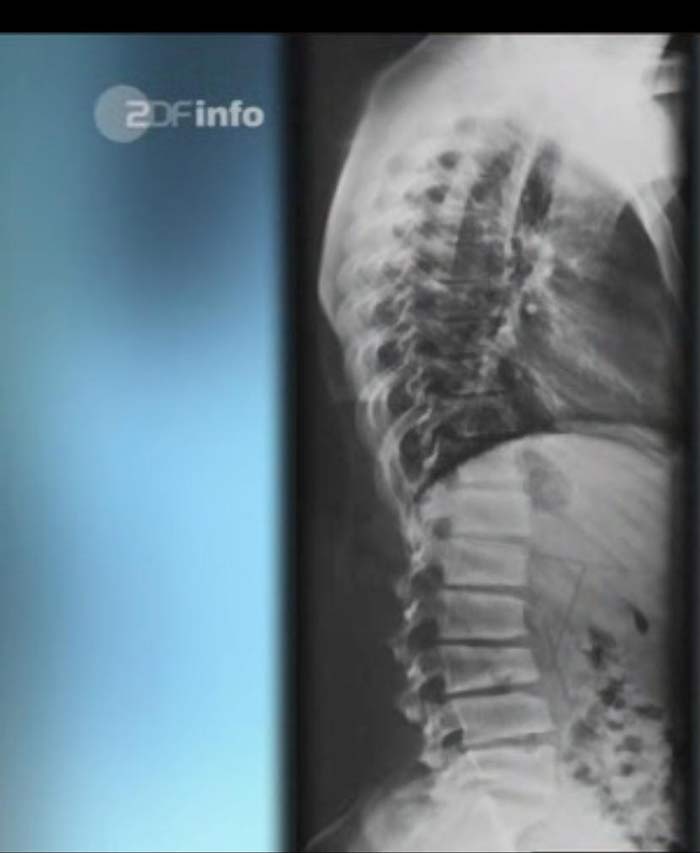

BWS-Kyphosewinkel 19°

LWS-Lordosewinkel 75°

HWS-Lordose aufgehoben

Schmorl'sche Knötchen zwischen L2-4

Das Bild soll nur die Form der Wirbelsäule wiedergeben, die Wirbelkörper sehen teilweise etwas anders aus.

Es handelt sich um einen M. Scheuermann an der LWS, was viel seltener und leider auch häufiger mit Schmerzen verbunden ist. die meisten lumbalenScheuermänner gehen auch eher mit eiem Verlust der Lendenlordose als mit einer Hyperlordose einher. (in dem Fim sieht man einen auf dem Bildschirm)

Hier ist die primäre Pathologie in der LWS(75°) und die BWS muss das kompensieren und ist deshalb zu flach. In so einem Fall wäre ich auch mit einer OP viel zurückhaltender, weil man ja die LWS operieren müsste und das geht dann natürlich mit einem Verlust an Beweglichkeit einher.

Ist dieses Bild gemeint? Das ist der erste typische Scheuermann Typ II den ich sehe.f.geiger hat geschrieben:Es handelt sich um einen M. Scheuermann an der LWS, was viel seltener und leider auch häufiger mit Schmerzen verbunden ist. die meisten lumbalenScheuermänner gehen auch eher mit eiem Verlust der Lendenlordose als mit einer Hyperlordose einher. (in dem Fim sieht man einen auf dem Bildschirm)